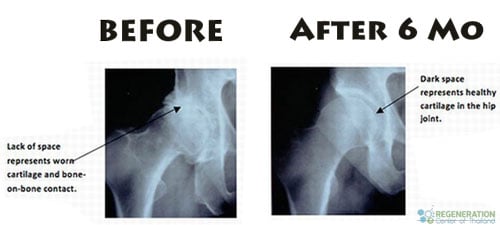

Our hip and shoulder stem cell therapies are combined with enriched blood PRP (platelet rich plasma) and growth factors to allow an effective and 100% non-surgical solution for our patients with cartilage damage, DDD, Spinal Injuries or who may be considering hip replacement surgery or hip resurfacing to try to resolve the chronic hip pain.[1] Our treatment protocol is ideal for mild and moderate cases of ligament, cartilage damage and for those that want to regenerate/reverse hip problems without surgery using enriched lab concentrated mesenchymal cell injections using the patient’s own stem cells (autologous – for mild conditions ) or immunosystem matched allogeneic stem cells ( for moderate to severe conditions.) This unique protocol allows our orthopedic stem cell doctors to target the problem at the root and treat it using enriched tissue manipulation techniques that allow treated arthritic knees and hips to naturally heal itself without need for invasive surgery.[2]

Our orthopedic Hip Cell Therapy works by targeting the areas of arthritis or injury with both clinical-grade stem cells and ( PrP ) platelet-rich plasma. The cultured stem cells and paracrine cell signaling act as a biological seed with PRP acting as the fertilizer to fortify the cells and helps quickly heal the areas of distress. Our unique 2-week treatment course uses PRP with cell-specific growth factors and rich platelets found in the blood circulatory system. Unlike most 1 day treatments, these additional steps in our therapy help boost cell signals while simultaneously providing nourishment for the orthopedic stem cells to flourish for multiple cycles and help develop the introduced cells into new and healthy joints, tendons and ligaments. The Regeneration Center uses a proprietary closed-system for MSC+ cell culturing to help triggers rapid stem cell development.

Regenerative medicine might not be the final answer for all patients with degenerative hips and neuropathy, however, most cases patients treated with MSC+ stem cells are successful, and help our patients avoid the pain, downtime, disability and most importantly risk that is associated with a major surgery like total hip replacement. Our treatment is minimally invasive and there is very little recovery time needed after treatment. Most patients usually only report slight soreness in the treated areas with minimal bruising for 24-48 hours post-therapy. Our center has never had any patients experience adverse effects as all cells are tested and certified before implantation. After the hip join treatment, patients are encouraged to start a hip osteoarthritis diet with regular hip rehabilitation to help re-strengthen the hip joints back to proper function. Hip stem cell treatments are very safe, and for severe cases, can also be repeated after 6-12 months (if necessary) to achieve optimal results. For patients with severe hip damage, stem cells alone might not be sufficient. For severe cases, we offer the world’s first combo-treatment that combines micro-surgery with stem cells (after surgery) to expedite and normalize the healing process with minimal scarring.